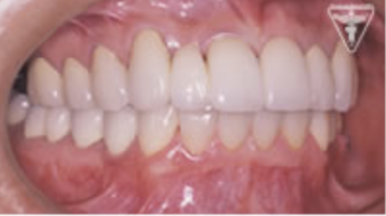

治療後

初期治療を経て歯周外科、歯内療法により病巣の消失が認められ改善された。

右上は将来人工歯根による処置の為GBRを行った。

咬んだ感じが軽くなり、よく咬めると評価を頂きました。